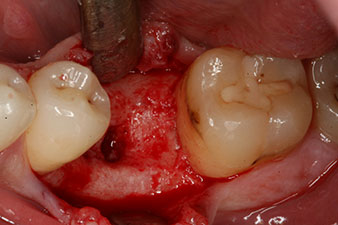

No obstante, seis semanas después de la extracción, tras la disección del colgajo mucoperióstico, se observó una osificación incompleta en el área del antiguo alvéolo mesial.

Tras la extirpación minuciosa del tejido de granulación, se incorporó el implante tal como se había planificado (blueSky, bredent).